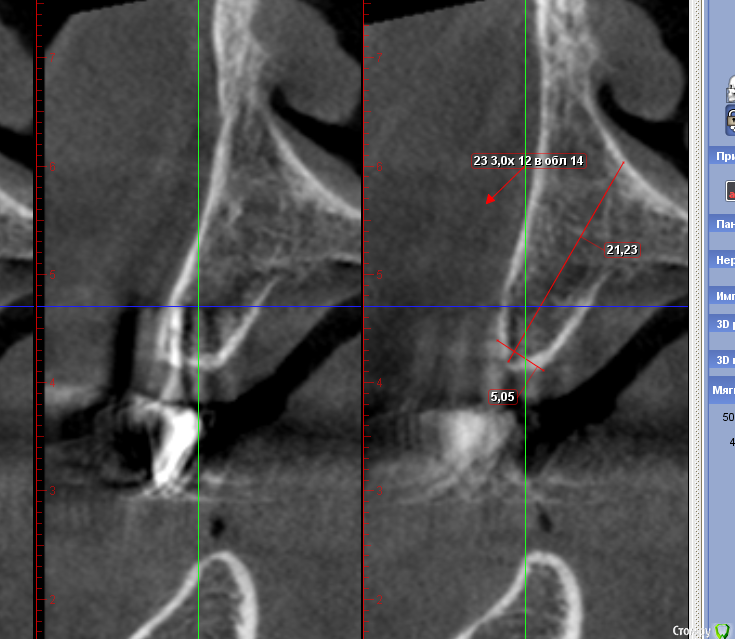

Sergiosse Опубликовано 4 марта, 2016 Поделиться Опубликовано 4 марта, 2016 Женщина 67 лет.полная адентия в\ч.Планируется установка 2-х Остем мини 3,0х12мм. с лабильными болл аттачменами. Ширина гребня 5мм.Есть сомнения выдержит ли кость нагрузку на трехмилиметровых импл.Альтернатива- расщепление и имплант 4.2мм. Заранее спасибо. Ссылка на комментарий

Аслан Опубликовано 4 марта, 2016 Поделиться Опубликовано 4 марта, 2016 как вариант, просто установить чуть глубже и немного досыпать вестибулярно при такой оси постановки импланта, как показаны измерения. Ссылка на комментарий

Nazim_NV86 Опубликовано 4 марта, 2016 Поделиться Опубликовано 4 марта, 2016 (изменено) у Osstem нет 4.2 диаметра. Все с шагом 0,5. Не советую расщеплять. Направление, выбранное на кт неверное. Ставьте не по центру гребня, а параллельно вестибулярной кортикалке.Зачем мини 3,0, когда можно 3.5х13 утопить? поставьте с помощью экспандеров и сразу фдм диаметром 4 если торк выше 45. Изменено 4 марта, 2016 пользователем Nazim_NV86 Ссылка на комментарий